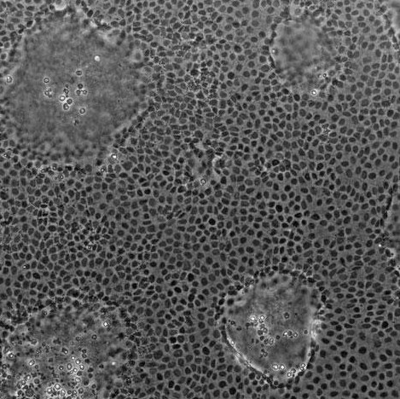

Increased intestinal permeability has been described in a numberCaco-2 cells of diseases, including inflammatory bowel disorders (IBD)1, celiac disease2, and in conditions not primarily associated with the intestines.3 Even though the etiology of these diseases is far from clear, it is now widely accepted that the gut barrier plays an important role in health and disease.4 Studying intestinal permeability is critical to the development of therapeutics targeted at alleviating and avoiding the crippling symptoms associated with gut barrier disruption.Mounting data from in vivo and in vitro studies show that intestinal permeability is influenced by stress, diet, microbial changes, and underlying genetic susceptibility. The complexity of intestinal permeability-related diseases makes it difficult to find suitable research models, let alone models that can be scaled up for high-throughput target validation and drug discovery purposes.5 While animal models have helped advance our understanding of IBD mechanisms, manipulating individual parameters such as epithelial barrier function and cell-type specific activation is challenging.5When grown on permeable membranes, human colon adenocarcinoma (Caco-2) cells differentiate to form confluent monolayers, which display functional and structural characteristics of enterocytes (the cells that line the small and large intestine).6–8 Caco-2 cells can be used to study innumerable topics, including inflammatory triggers, bioavailability, permeability, and toxicity.9 Caco-2 cells are also considered to be the gold standard for in vitro prediction of intestinal drug permeability and oral drug absorption. However, creating intestinal permeability models with Caco-2 cells isn’t always as smooth-sailing as you might hope.Here are seven problems you might be facing when creating your intestinal permeability model with Caco-2 cells:1. Caco-2 cell tolerance of DMSODimethylsulfoxide (DMSO) is a standard solvent used forDMSO preparing stock solutions and is one of the principal additives in assay buffers.10 Although cytotoxic at high doses, it is often used in low concentrations as the control reagent during exposure, and in cryopreservation. The tolerance for DMSO varies across cells and transport proteins, and its possible effects on your results are worth bearing in mind; a recent epigenetic study revealed that low doses of DMSO induced major changes in DNA methylation in cardiac (but not hepatic) microtissues.11Above a certain threshold, DMSO can affect cell growth, protein stability and aggregation, and binding of drug compounds.10,12 Some protocols advise running a solvent tolerance test to ensure your results are not affected by the concentration of DMSO used in your cell culture experiment.6,102. Caco-2 cells taking too long to growIf you’ve ever grizzled about your Caco-2 cells takingCaco-2 Grow Slowly too long to grow, know that you are not alone. Slow-growing cells can be frustrating, especially when the problem significantly drags out your experiments, and limits the number of experiments you are able to complete.Troubleshooting can be time-consuming as there are many variables and possible reasons for slow growth; mycoplasma contamination and an overly dense feeder layer are two major possibilities.3. Overcrowding of Caco-2 cellsThe design of transport assays is based on the assumption that cells are organized in a monolayer, mimicking enterocytes in vivo. However, dome formation of Caco-2 cells can occur when a cell layer is pushed away from the culture dish by the accumulation of fluid beneath.13 This distortion can create fluid pockets, leading to uneven treatment distribution, and inadequate oxygen supply.14 These factors can compromise your transport assay results. Overcrowding can also occur when cells become too confluent, and differentiate before you are ready to run your assay. Subculturing cells before they have reached confluence can help cells to form a more homogenous and polarized monolayer.15 One protocol suggests subculturing cells when they have reached 50% of confluence, in contrast to an existing recommendation of 80%.154. Stability or instability over timeThe number of times a cell culture is subcultured, or transferred from one vessel to another, is known as the “passage number”. Higher passage numbers and longer culture times can compromise genome stability and alter critical cell characteristics. Caco-2 cells are no exception; gene expression, phenotype and signaling pathways have been reported to drift over time in Caco-2 cells.16 Drifting gene expression levels can affect cell function and contribute to erroneous results.Protocols generally recommend limiting continuous cell cultures to three months, or a particular number of passages. Excessive time in culture can also increase the risk of cell culture contamination, which is another reason to keep culture times on the shorter side where possible. There is no “magic number” of acceptable passages, and constant monitoring for changes in phenotype and cell density is essential.5. Potential scalability for drug discoveryFrom a drug discovery perspective, models are needed thatPills allow researchers to screen thousands of drug candidates. Conventional membrane insert-based systems are limited in their scalability on this level, and typically do not cater for 3D cellular models – an aspect that is desirable for improving physiological relevance. While you might have the ideal cell type for modeling intestinal permeability, having the potential to incorporate 3D models or other cell types would be highly beneficial.176. Research costs associated with compounds, media, and reagentsWhenever you are troubleshooting issues with culturing your Caco-2 cells, you could potentially be wasting huge amounts of money on expensive compounds – not to mention copious amounts of fetal bovine serum and other reagents. Any technology that reduces your reagent, cell, and time consumption can significantly reduce research and development costs.7. The need for specialized instruments and equipmentModern drug discovery approaches rely on high-resolution kinetic measurements and image-based readouts. However, conventional transwell models are poorly suited to the instruments and imagers required for kinetic measurements.17 Having a platform compatible with automated plate readers, microscopes, and other technologies could help researchers to extract critical information about intestinal permeability from their Caco-2 cells.Some research groups working with Caco-2 cells might find they have a shortage of laboratory personnel with the specialized skills required for setting up desired experiments. Certain research models may require staff to be knowledgeable in microfluidics, or experienced in assessing barrier integrity. The transepithelial electrical resistance (TEER) is a measure of the integrity of a monolayer corresponding to barrier function, with differentiated polarized cells that have formed tight junctions.18 TEER is used to gauge the effect of different exposure times and concentrations. Without prior experience, navigating the literature surrounding TEER techniques19 can be challenging.One Nature Protocols paper states that “Given the necessary care and attention, most cell lines are easy to maintain and grow”.20 Despite this, most researchers still find there are many obstacles to navigate when working with Caco-2 cells. If Caco-2 cells are critical to your work, be sure to check this blog post where we will show you how you can grow your intestinal permeability models in less than five days.Learn more about MIMETAS organ-on-a-chip technology >>